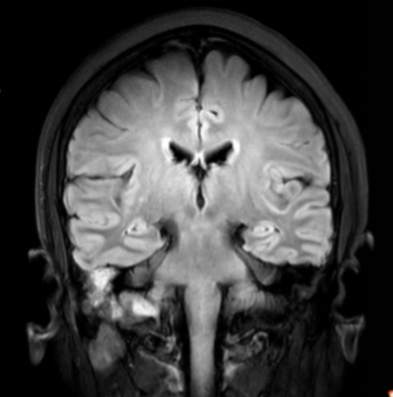

(2023-05-15 10:00,本院)行磁共振(颅脑)检查提示:右侧乳突区异常信号,考虑恶性、软骨来源肿瘤,软骨肉瘤可能性大。(集体讨论意见);脑内散在多发缺血灶。

(2023-05-12 10:15,本院)行CT(颅脑)检查提示:右侧颞骨广泛骨质破坏,伴巨大软组织肿块,性质待定,考虑肿瘤性病变,颈静脉球瘤?软骨源性肿瘤?请结合临床及病理进一步明确。

术后复查MRI: